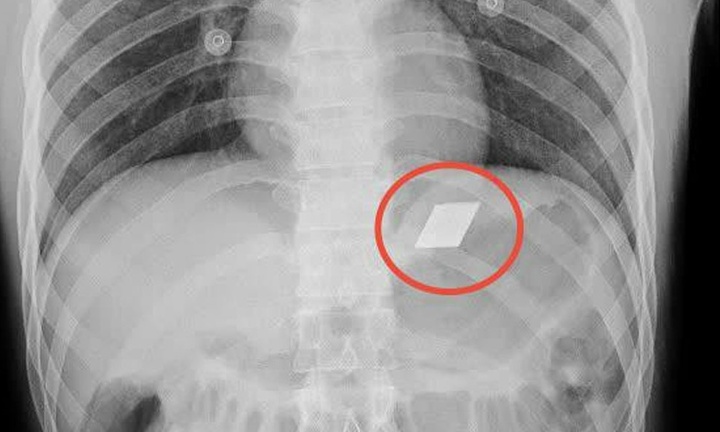

Nội soi gắp thành công chiếc chìa khóa trong dạ dày bệnh nhi 14 tuổi

Các bác sĩ tại Bệnh viện Sản - Nhi tỉnh Quảng Ngãi vừa lấy thành công một chiếc chìa khóa cửa kèm vòng sắt ra khỏi dạ dày nam thiếu niên 14 tuổi.